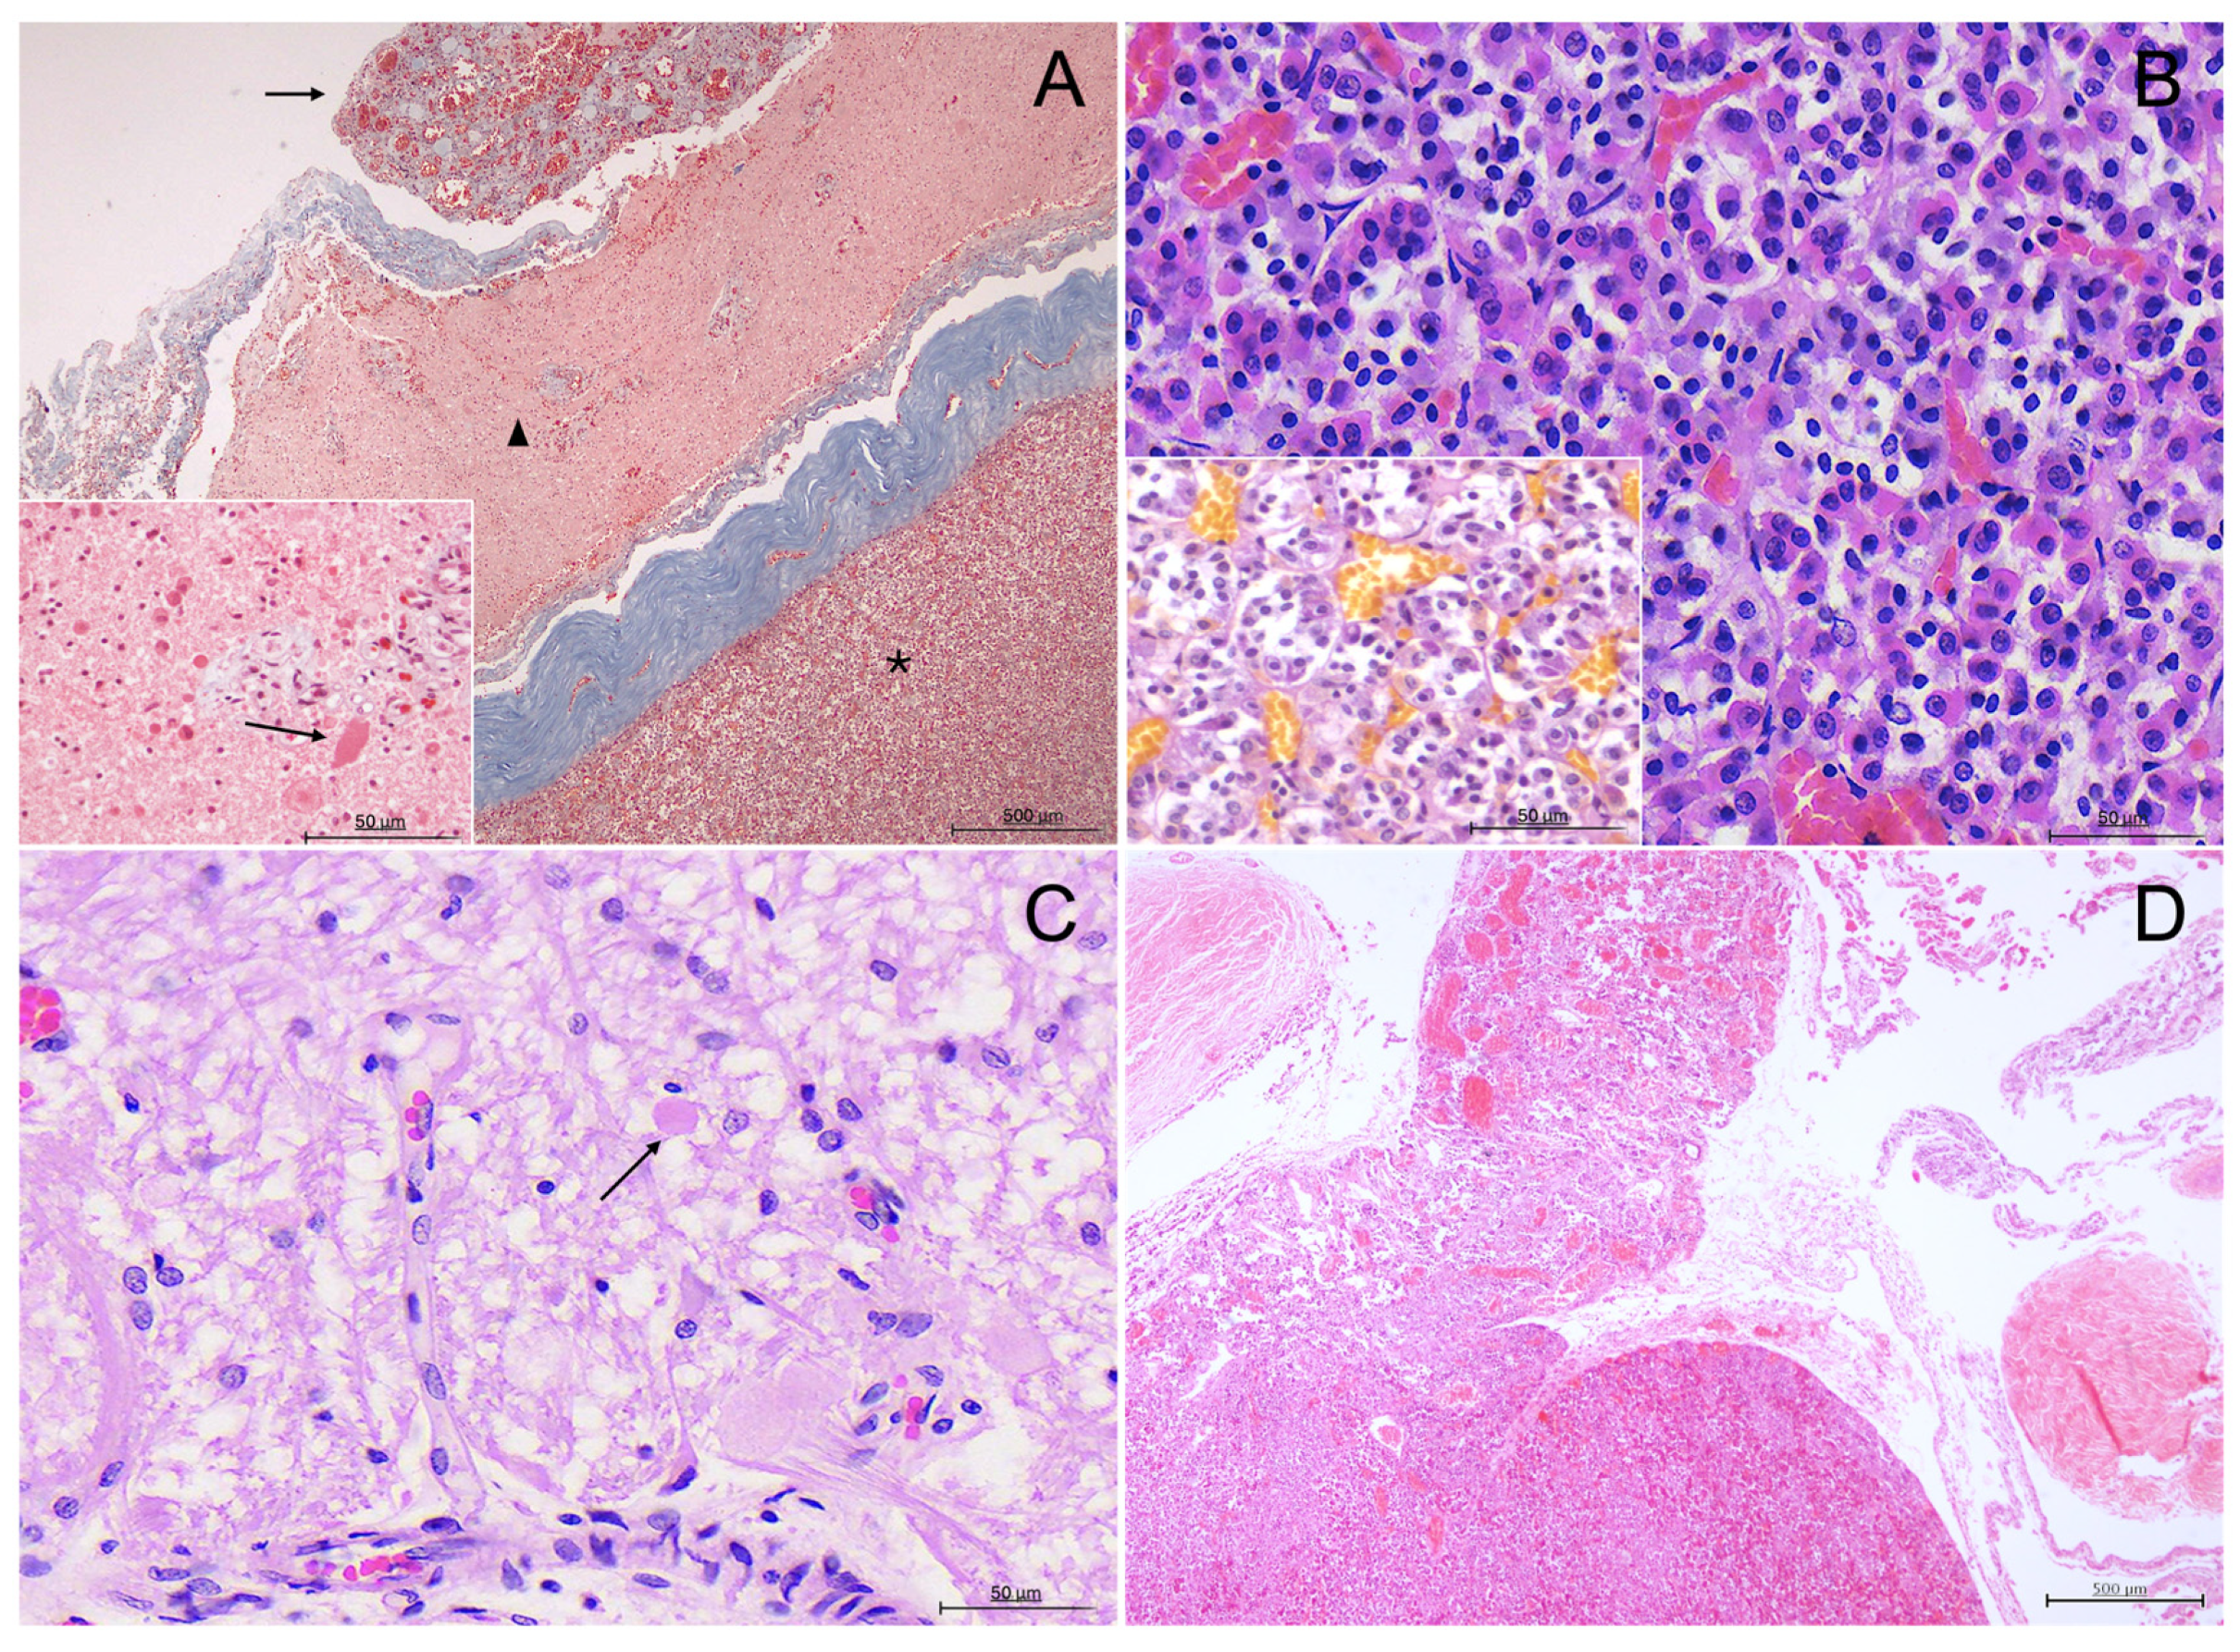

3.3. Histological Description

3.4. Inmunohistochemical Study

3.4.1. ACTH Labelling

3.4.2. MSH Labelling

3.4.3. TSH Labelling